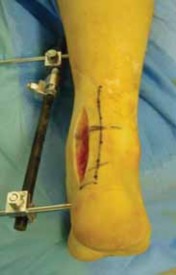

A foot and ankle external fixator must be constructed ( TECH FIG 6).

Initially, two 4-mm external fixation half-pins are inserted bicortically into the anterior distal third of the tibia.

A 4-mm half-pin is inserted bicortically into the base of the first and fifth metatarsals.

Finally, a 4-mm half-pin, or transfixion pin, is advanced from medial to lateral, bicortically, through the tuberosity of the calcaneus.

An external fixation rod connects the two metatarsal base pins, forming a midfoot unit. It is important to leave excess rod on each end of the midfoot unit for further tibial-rod attachment.

Next, an isolated, long external fixation rod is attached to the medial end of the midfoot unit and to the distal tibial half-pin, restoring neutral plantarflexion of the ankle.

A second, long external fixation rod is attached to the lateral end of the midfoot rod and connected to the proximal tibial pin, controlling ankle varus and assisting dorsiflexion.

Finally, external fixation rods are added, connecting the calcaneal pin to both the medial, midfoot rod and either tibial half-pin for increased frame rigidity and possibly to distract the subtalar joint.